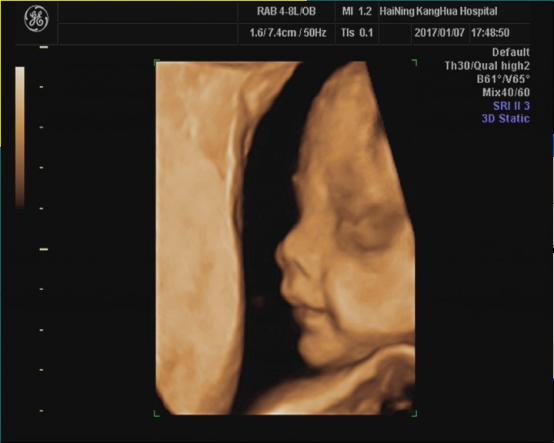

海宁康华医院“胎儿三维彩超检查”,为您创造“透视”条件!

胎儿三维超声检查最佳时间:

22—24周(备注:双胎不做三维超声检查)